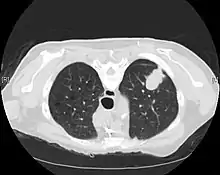

Imaging

A chest x-ray (radiograph) is often the first imaging test performed when a person presents with cough or chest pain, particularly in the primary care setting. A chest radiograph may detect a lung nodule/mass that is suggestive of cancer, although sensitivity and specificity are limited.

CT imaging provides better evaluation of the lungs, with higher sensitivity and specificity for lung cancer compared to chest radiograph (although still significant false positive rate[27]). Computed tomography (CT) that is specifically aimed at evaluating lung cancer includes the chest and the upper abdomen. This allows for evaluation of other relevant anatomic structures such as nearby lymph nodes, adrenal glands, liver, and bones which may show evidence of metastatic spread of disease.[4] Indeed, the US Preventative Services Task Force recommends annual screening with low-dose CT in adults aged 55 to 80 years who have a 30 pack-year smoking history and currently smoke or have quit within the past 15 years, with certain caveats (see Lung cancer screening).[28]

Nuclear medicine imaging, such as PET/CT and bone scan, may also be helpful to diagnose and detect metastatic disease elsewhere in the body.[7] PET/CT uses a metabolically active tracer that allows clinicians to identify areas of the body that are hypermetabolic. Increased uptake of the tracer occurs in malignant cells and areas of inflammation or infection. Integrating the imaging reflective of metabolic activity with normal CT imaging allows for higher sensitivity and specificity compared to PET alone.[4]

MRI is reserved for patients with advanced disease where intracranial, or brain, involvement is likely. It is also helpful for evaluating the extent of chest wall, diaphragmatic, brachial plexus (such as in the case of superior sulcus tumors), or spine involvement.[4]